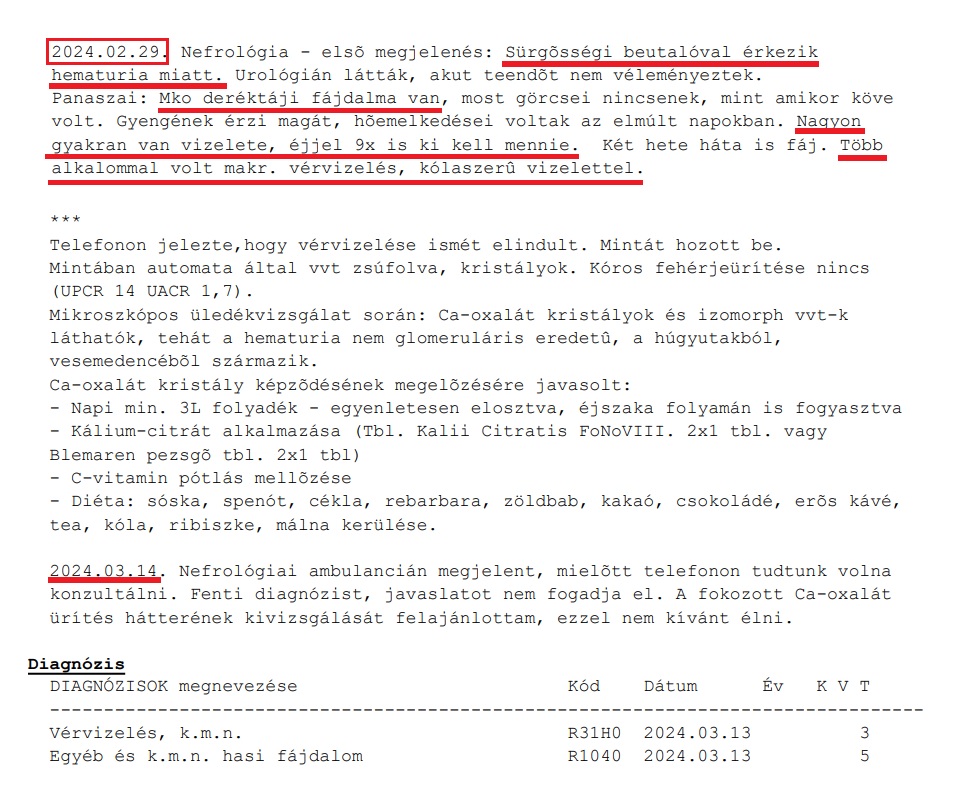

A fiam rohant Jordán doktor sürgősségi beutalójával az I. Belgyógyászati Klinika nefrológiai ambulanciájára, hogy felvegyék. Dr Ledó Nóra nefrológus ambulánsan „felvette”. Majd annak ellenére, hogy Zsolt közölte vele, hogy 6. napja szed antibiotikumot, Supraxot (Cefixime), nem érdekelte, szedése ellenére utasította fiamat tenyésztéshez vizeletminta leadására (durva szakmai hiba). Természetesen így a baktériumtenyésztés negatív lett. Ezért a fiamnak nem adott antibiotikumot, és kijelentésszerűen beírta az EESZT-jébe, hogy „uroinfekció nincs, antibiotikum adása nem indokolt”. Pedig hozott – 2 napos – leletén 650 vörösvértest/látótér szintű vérvizelés, fehérjevizelés volt, az általa készítetten pedig „sok baktérium/látótér” – az antibiotikum szedés ellenére. Emellett a klinikai tünetek: elviselhetetlen vesefájdalom, csupán éjszaka 9-10 vizelet, hányinger, napi 5-6 hasmenés. Ezek ellenére Ledó Nóra nem vette fel a fiamat kórházi kezelésre és nem adott IV antibiotikumot, pedig ilyen urológiai-nefrológiai állapottal napokon belül kórházban kezelnek mindenkit, minden civilizált országban – ez meg a főváros I. számú Belgyógyászati Klinikája!

11./ Március 13. Újra Semmelweis Egyetem I. sz. Belgyógyászati és Onkológiai Klinika: Dr Ledó Nóra

A fiam látta, hogy reggel az EESZT-be bejegyezte Ledó Nóra, hogy nincs nefrológiai teendő, a továbbiakban keresse fel háziorvosát, akinél 3-4 havonta csináltasson vizelet és vérvizsgálatot. Mintha a fiamnál minden rendben lett volna! Pedig ekkor már több mint 1 hónapja szenvedett kezeletlenül, nézni alig lehetett: Éjjelente 8-10 vizelet, délelőtt 5-6 hasmenés, 0-24 kétoldali elviselhetetlen vesefájdalom, hőemelkedések, hányinger, gyomortáji fájdalom, nagyon magas pulzus. (Súlyos vesemedence-gyulladás tünetei!) Éppen amikor a fenti sorokat Dr Ledó beírta az EESZT-be és lezártnak tekintette Zsolt esetét, visszatért a vérvizelés!

A fiam már nagyon-nagyon rosszul volt, 6 hete volt kezeletlenül – és nem vette fel ez az általam orvosnak nem tekinthető nő kórházba kezelésre! Előtte két nappal, 2024. március 11-én telefonon kérte a fiam Dr Ledó Nórát, hogy mivel nagyon rosszul van már, súlyos fájdalmai vannak, hogy vegyék fel a kórházba, hogy ki tudják vizsgálni és kezeljék végre. Ledó Nóra azt felelte, „akkor menjen el a sürgősségire, már mondtam 2 hete is”…”nem tudnám beadni az igazgatónak, nem venné fel, nem vennénk fel!” – a fiam teljesen lefagyott, nem tudta mit tegyen, hová mehetne még, mit csináljon…

12./ Március 14. Ismét Semmelweis Egyetem I.sz. Belgyógyászati és Onkológiai Klinika: Ismét Dr Ledó Nóra

Csütörtöki nap, Dr Ledó Nóra hivatalos rendelési ideje a Semmelweis I. Belgyógyászati Klinikán. A friss, ijesztő eredménnyel és állapottal, a váróban álltunk Zsolttal, amikor Ledó Nóra ajtót nyitott és a következőt mondta:„Ez…ez rémisztő, hogy csak úgy megjelennek itt…”, mire a fiam mondta, hogy a leleteredménye a rémisztő és az amilyen állapotban van. Zsolt megkérdezte, „miért viselkedik ilyen agresszíven?” – „Azért, mert ma még nem ettem, azért.” – mondta. A fiam hozzátette, „Másból meg folyik a vér és napok óta nem evett!” – majd Dr Ledó visszalépett az orvosi szobába és ránkcsapta az ajtót. Erre az egészre aztán nem számítottunk, különönösen a fiam ekkor már hetek óta tartó kínzása (kezeletlensége) és friss leleteredményei tükrében, meg azért sem, mert rendelési idő volt, ez pedig egy kórház, ami Ledó Nóra munkahelye, akihez visszajáró betegnek számított a fiam – akit már rég fel kellett volna vennie. Ehelyett hetek óta nem csináltak semmit vele, és focilabdaként rugdosták 3 megye között.

Valójában az orvosnak örülnie kellett volna, hogy a beteget felhozták Budapestre, és neki csak azonnali betegszállítással el kell helyeztetnie egy kórteremben és megkezdeni az azonnali kezelését. De Ledó Nóra nem így gondolta, továbbra is megtagadta a kórházi felvételt. Az esetről ekkor már hangfelvétel készült, ami igazolja a fent leírtakat, mert már tarthatatlan volt, amit velünk, elsősorban a fiammal csinált. A hangfelvételen hallatszik, ahogy szegény fiam mondja, „Hány pozitív laborleletet hozzak még, hogy komolyan vegyék?” – „Mi komolyan vesszük”, mondta hetykén Ledó Nóra, majd pár perccel később már arról beszélt, hogy „Nyugodtan el lehet menni innen, ha nem tetszik valami, lehet keresni másik kórházat.” – Mondta ezt úgy, hogy az élete az objektív eredmények alapján is veszélyben volt. Zsolt szervezete az összeomlás alatt volt, de ő nagy küzdő és tűrte, ami nagy baj utólag nézve. És az is nagy baj, hogy én mint anya aki mindenhová elkísértem a fiamat, hagytam ezt. Neki kellett volna már mennem – azt érdemelte volna.

Az EESZT-be 13-án reggel beírt állításának ellentmondóan, miszerint ha visszatér a vérvizelés urológiai rekonzílium szükséges, ilyen nem történt, kiderült úgy gondolta ezt, hogy mi kérjünk elektív időpontot az urológiára és mi konzultáljunk az ottani urológussal, valamikor, majd… Ekkor már nem tudtuk eldönteni, hogy egy ennyire gonosz ember áll velünk szemben, vagy csak mi belőlünk próbál teljesen hülyét csinálni látva kiszolgáltatottságunkat, de utólag nézve, brutális, hogy meddig hagytuk, hogy ezt tegye velünk, és ezzel megássa Zsolt sírját!

Március 14-én kiállított közben egy olyan leletet, ahol a 10 pozitív, köztük súlyos nefrológiai paraméterekből, kiválasztott mindössze 2-t, a „vvt zsúfolva/látótér” és a „sok kristály” megállapításokat, a maradék 8-ról (például 7-szeres fehérjevizelés, gennyvizelés, baktériumvizelés) pedig nem írt semmit. Több liter víz fogyasztásáról írt, éjszaka is javasolva (miközben a fiamtól tudta, hogy éjszaka 9-10 vizelete van, vagyis így sem tud aludni, óránként felébred emiatt és a fájdalom miatt), továbbá „kezelése” a fiam számára közel 1,5 hónap kezeletlenség után, hogy kerülje a spenótot, rebarbarát, málnát, csokoládét, c-vitamint. És felháborodott, hogy személyesen felmentünk a súlyos leleteredmény után másnap 14-én, egy három napos ünnep előtt és nem telefonon akartuk letudni a fiam állapotát.

Ugyanis mint kiderült, esze ágában sem volt kórházba felvenni és azonnal kezelni a fiamat. Zsolt összeomló állapotát a fent írtakkal, mint pl a c-vitamin és kóla kerülése szándékozta kezelni. Megállapította, hogy a nagyfokú vérzés vagy a vesemedencéből vagy a húgyutakból származik, majd ezzel rendezettnek tekintett mindent.

Szinte sokkolt minket ez az egész. Az alább látható a március 13-ai, 14-ei beírás illetve hogy már február 29-én sürgősségi (egyébként három felkiáltójeles) beutalóval érkeztünk vérvizelés miatt, úgy hogy akkor már 3 hete tartott Zsolt súlyos állapota. Ekkor pedig már március közepét írtuk. Nem tudtuk, mit tegyünk. Ma már tudjuk, ezen a ponton volt az utolsó esélyünk, hogy a karhatalmat, rendőrséget kihívjuk és érvényesítsük a fiam betegjogait, mint az egészséghez való jogát, biztosított betegként az ellátáshoz való jogát. De akkor nem ezt tettük és nem sikerült megmenteni a fiamat a pokoli következményektől, ami ezután következett.